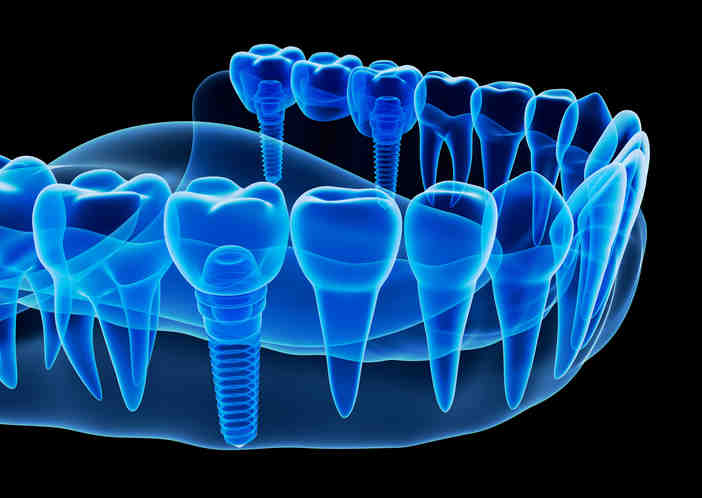

Cosmetic dentistry portland implants bone grafts

What is the best bone graft for dental implants?

Are bone grafts necessary for dental implants?

Bone implantation is not always necessary for the placement of dental implants, but in cases where this procedure is indicated, it can help to significantly improve the patient’s chances of good treatment results. Only your surgeon can determine the need for a bone graft, often using special imaging technology.

What happens if you don’t have enough bone for dental implants?

If you don’t have enough bone, the bone can be rebuilt. If you don’t have enough rubber, it can be added as well. This must be done before the implants can be placed. The treatment is called Bone Augmentation and has been used successfully for years.